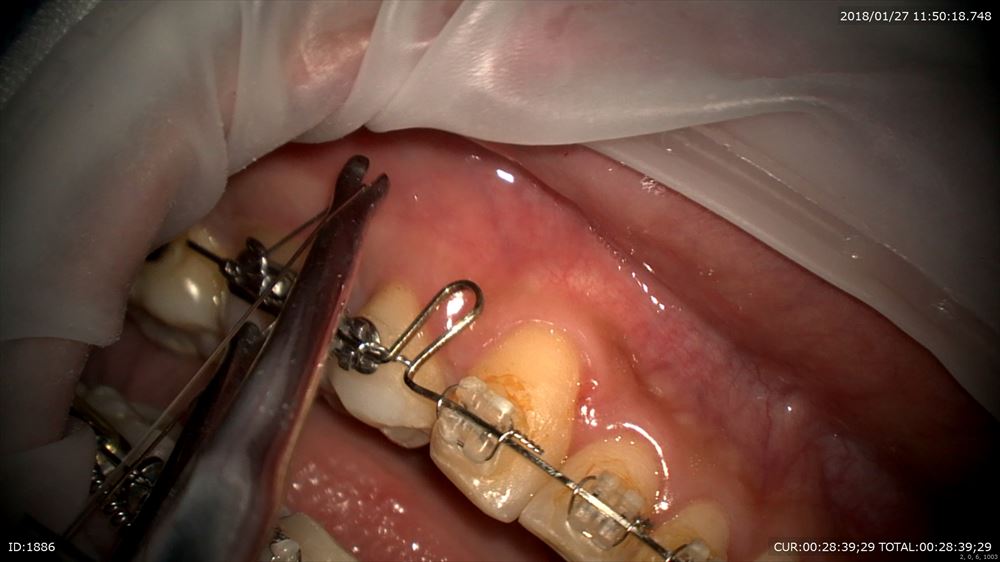

最後は矯正。4番の抜歯スペースのリトラクションの最終段階とトルクコントロール同時

マイクロで観察。トーイン。テイップバック

これでOK。春には外します!口元も綺麗になりました。